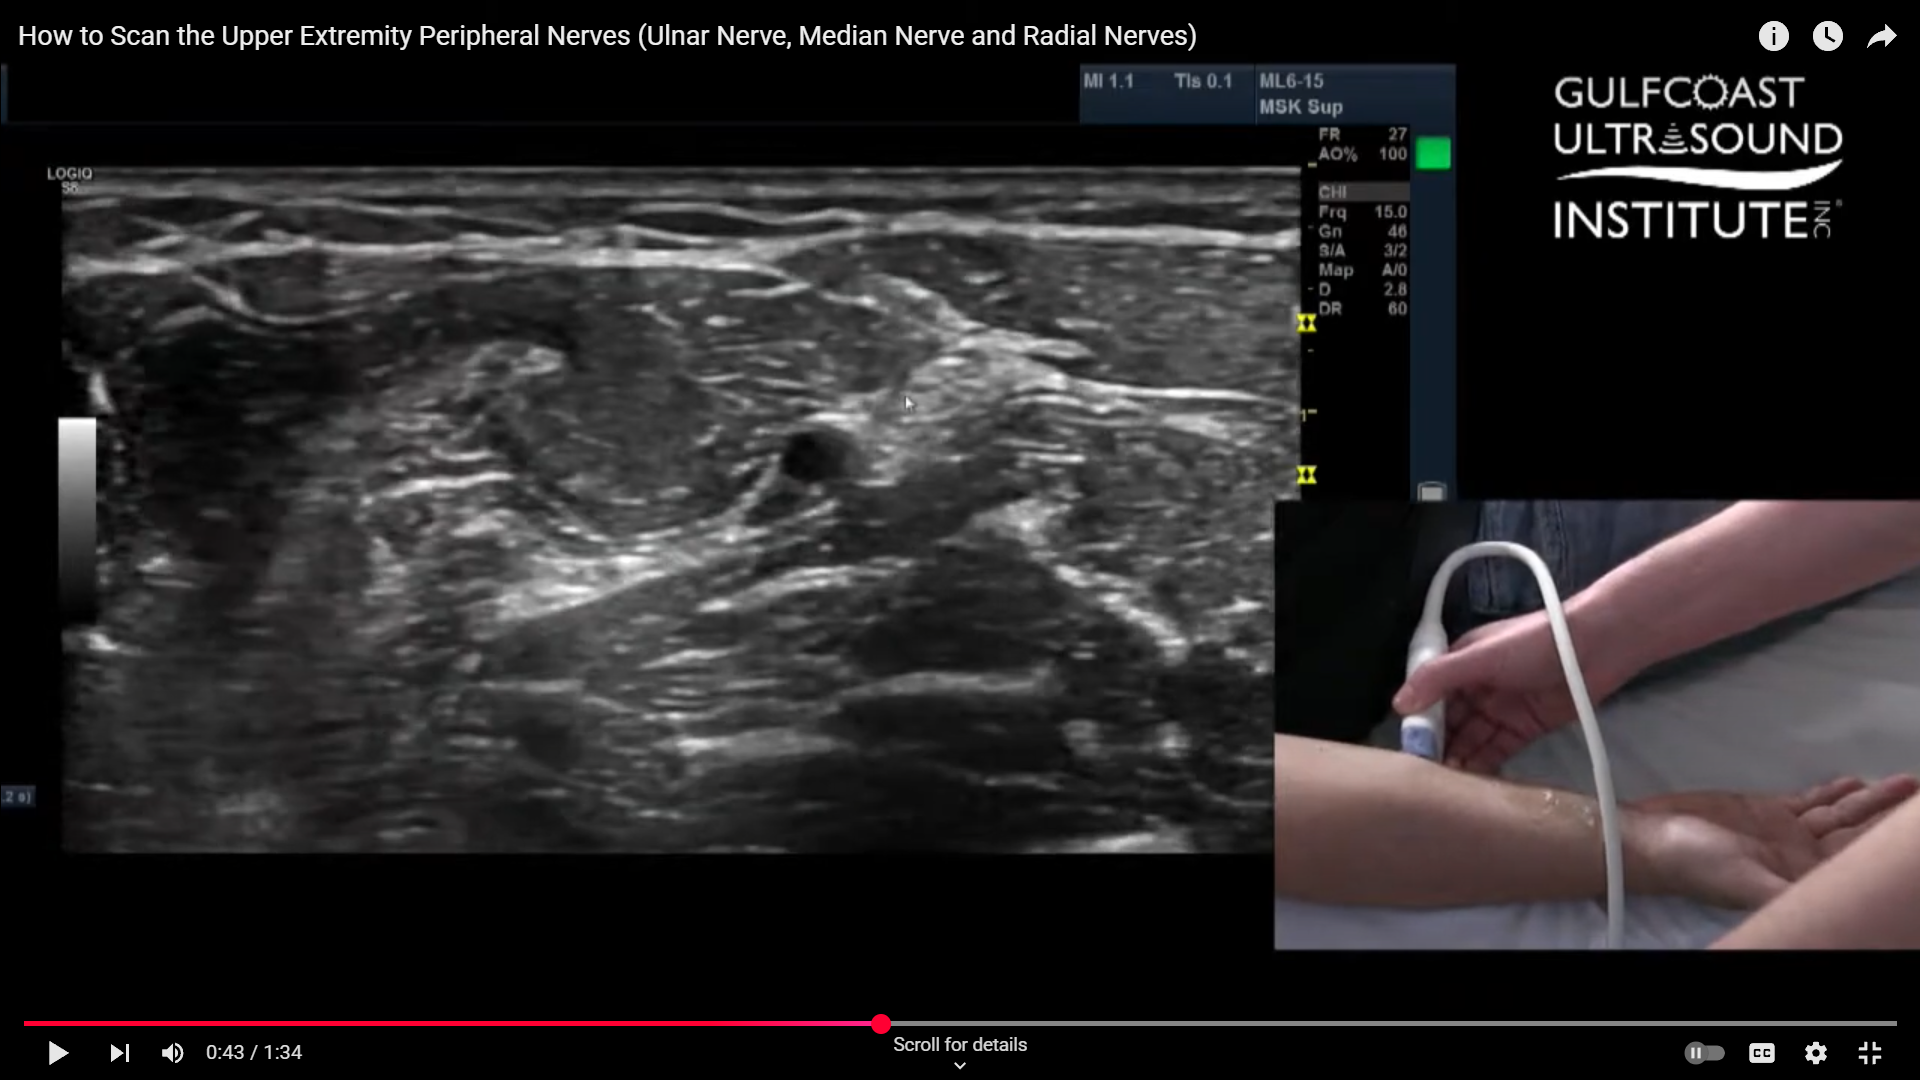

Ultrasound-guided nerve blocks have become a staple in regional anesthesia and pain management. When performed correctly, they're efficient, targeted, and greatly improve patient comfort and outcomes. Today, we’re walking through a practical and approachable technique for scanning the peripheral nerves of the upper extremity. Whether you're a beginner or brushing up on your skills, this step-by-step breakdown will help you navigate the anatomy and get confident with your probe placement.

Start with the Ulnar Artery as Your Landmark

The ulnar artery is your gateway. When scanning the forearm, begin by locating this structure. It’s typically easy to spot and sits right in the center of your screen when you're in the correct transverse view. Once you've found the ulnar artery, the ulnar nerve will be close by, running right alongside it, particularly at the distal end near the wrist. At this level, they’re nearly touching.

Scan Proximally to Watch the Nerve Diverge

As you slowly scan more proximally, up toward the elbow, you’ll notice the ulnar nerve begins to pull away from the artery. Around two-thirds of the way up the forearm, the nerve becomes more distinguishable and easier to isolate. This separation is helpful when prepping for a nerve block, as it creates a clearer visual window for needle guidance.

Identify the Median Nerve from the Same View

Once you're in that same mid-forearm area, glance medially. You’ll often spot the median nerve in that same imaging plane. With a bit of finesse, you can line up your probe to visualize both the ulnar and median nerves simultaneously. This is a huge advantage, because with one well-placed injection, you can block both nerves at once.

Locating and Blocking the Radial Nerve

Now for the radial nerve. This one behaves a bit differently. It splits just distal to the elbow, so you'll want your patient to slightly rotate their forearm into a "thumbs-up" position. This hand orientation gives you better access and a cleaner acoustic window. Place your probe along the mid-arm and start sliding it laterally. As you angle and tilt your probe slightly, you’ll see the radial nerve pop up between two muscle layers, nestled right in the fascial plane. It’s a distinct and satisfying view once you catch it.